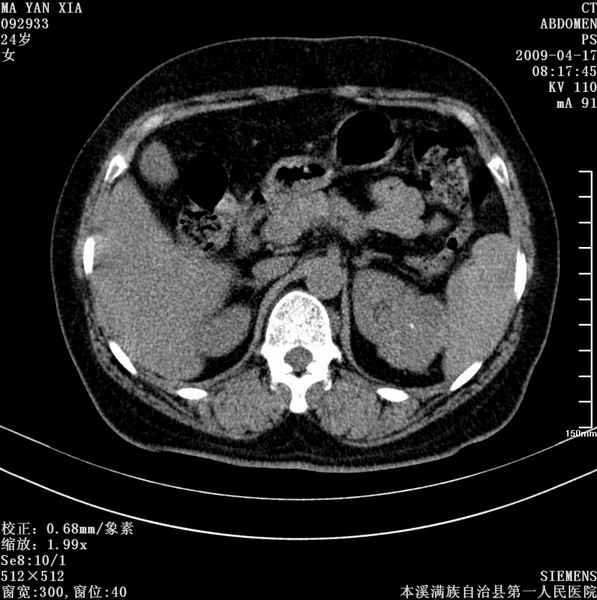

标题: CT19443:肾脏肿瘤两个区强化不一样。 [打印本页]

标题: CT19443:肾脏肿瘤两个区强化不一样。

女,51岁,体检时发现肾脏占位,建议ct增强。无任何自觉症状。

首先考虑左肾癌.

左侧肾脏占位,考虑肾癌。

左侧肾癌侵犯肾盂。

考虑左肾癌侵犯肾盂。